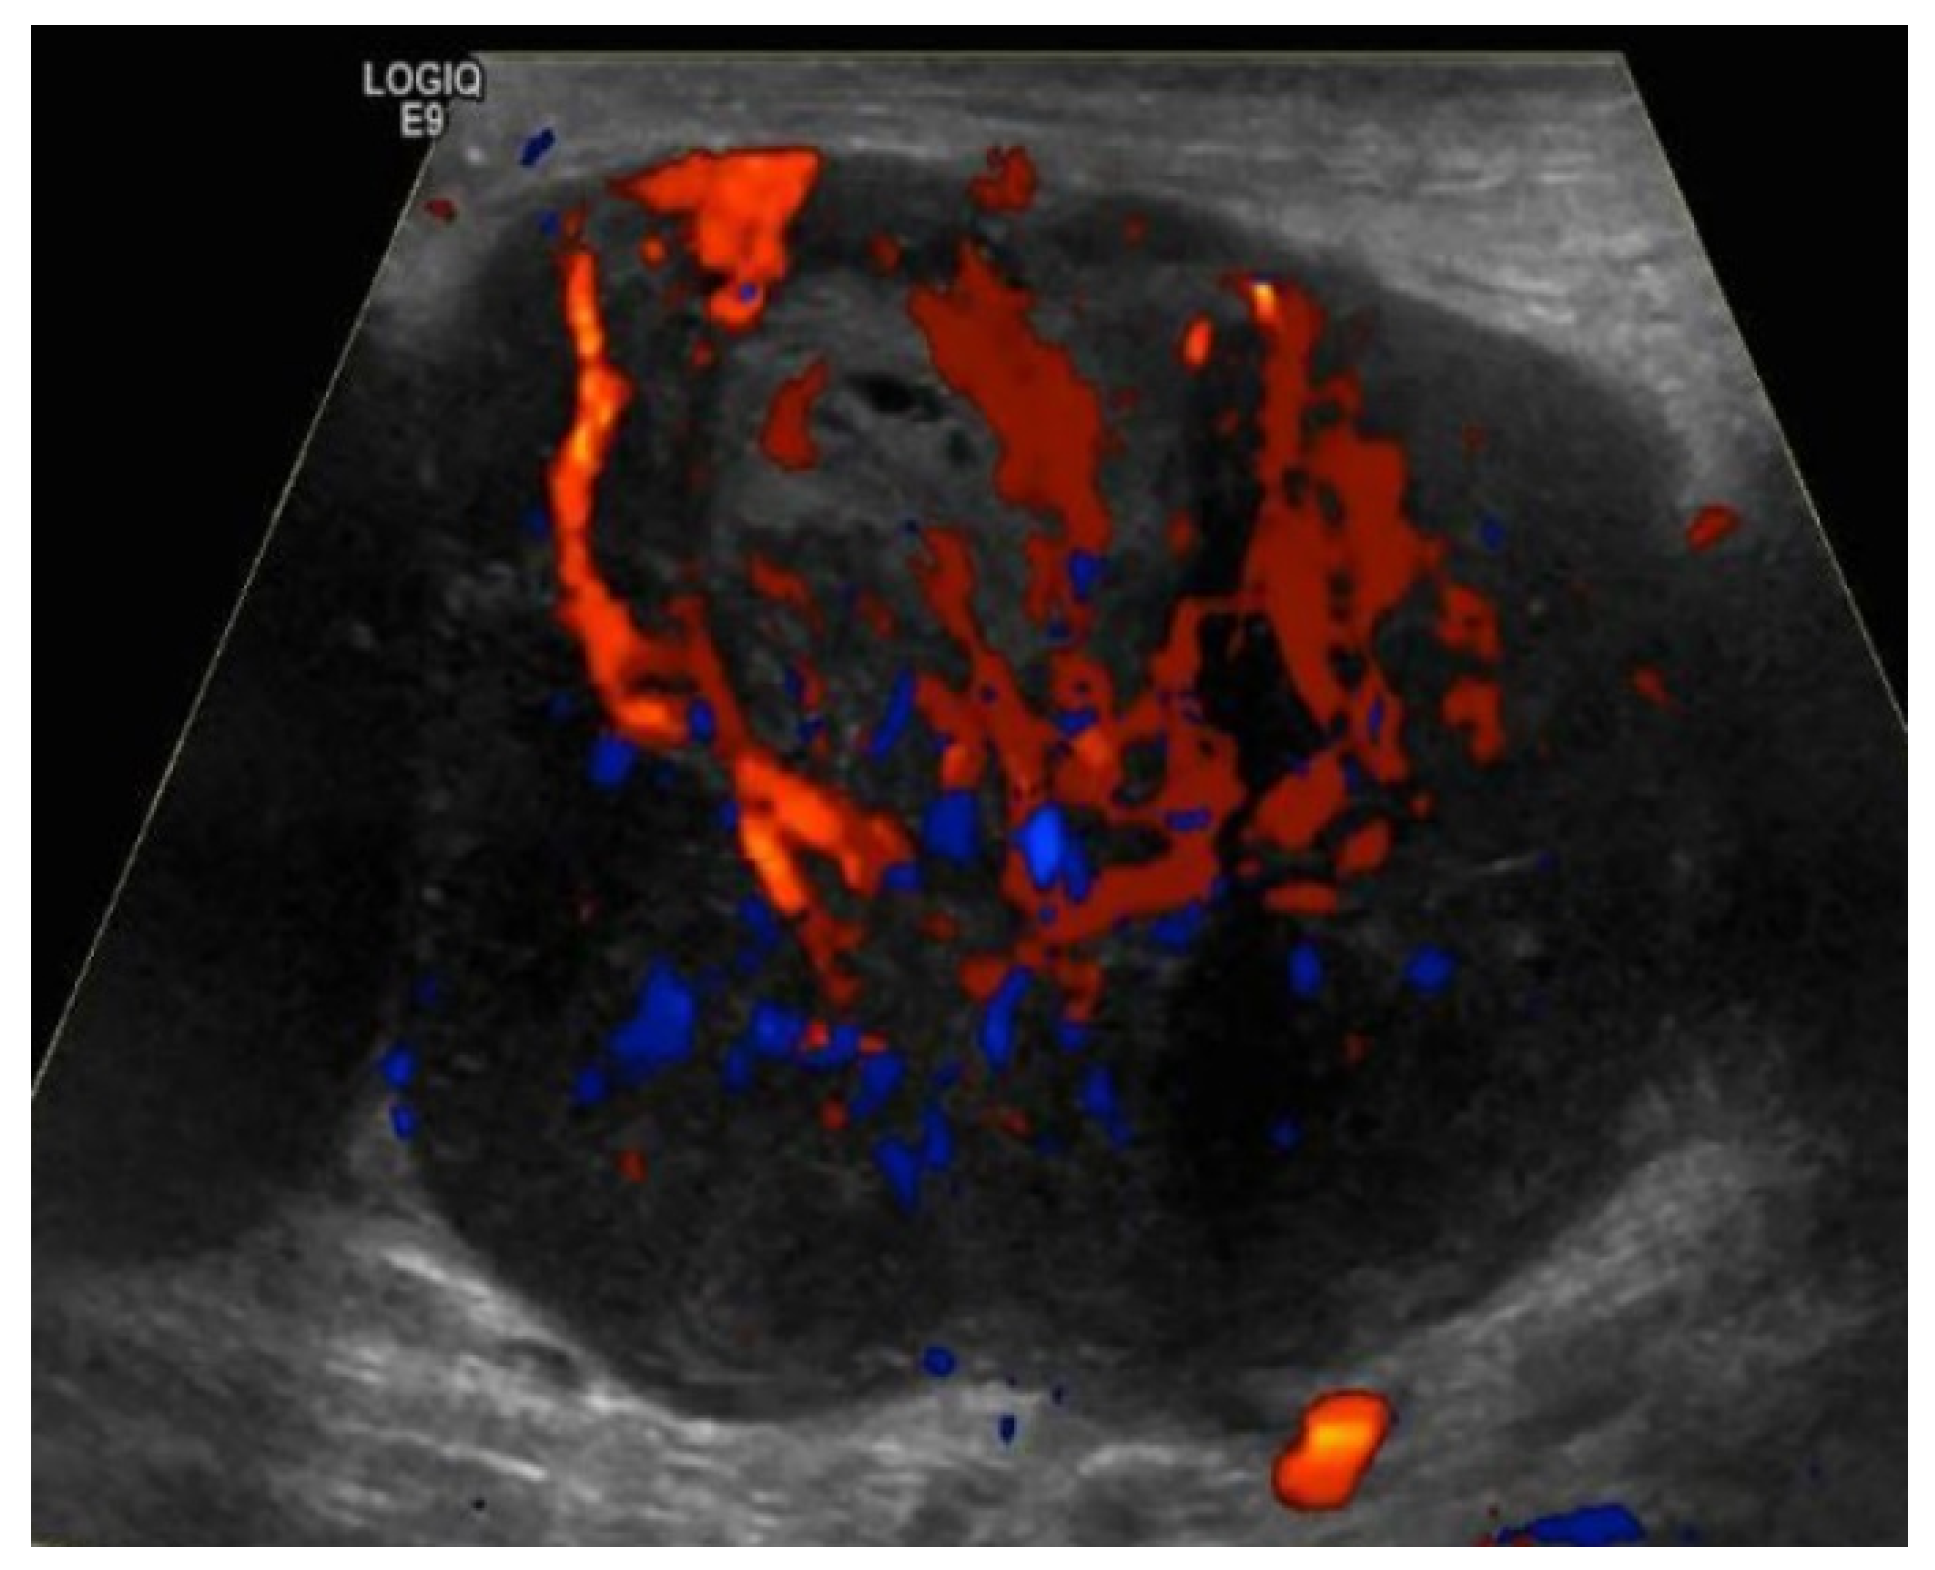

4.1.1. Ultrasound Evaluation of the Lymphatic System

| US Criteria | Benign Lymph Node | Malignant Lymph Node |

|---|---|---|

| Size | <1 cm in short axis | ≥1 cm in short axis |

| Shape | Oval or elliptical | Round |

| Border | Indistinct | Sharp |

| Echogenicity | Hypoechoic | Very hypoechoic |

| Hilum | Maintained fatty hilum | Absent fatty hilum |

| Vascularity | Avascular or hilar vascularity | Peripheral or mixed |

| Resistive index | Low | High |